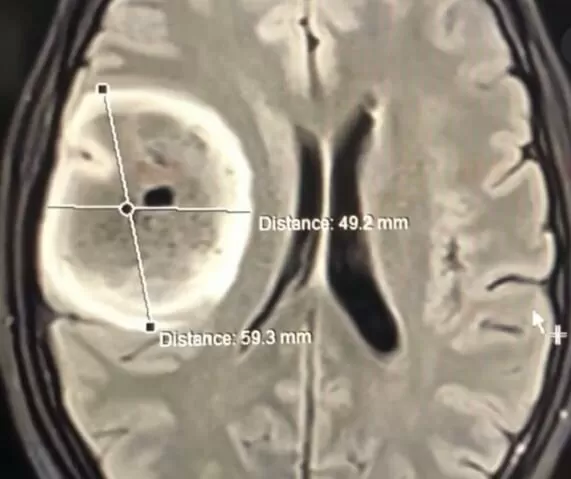

Астроцитома – пухлина мозку

Астроцитома належить до первинних пухлин мозку, і отримала свою назву через тип нервових клітин, з яких складається — астроцитів. Астроцити, або зірчасті нейрони, отримали свою назву через схожість із зірками – багато відростків, що відходять в різні боки від центру клітини. Головна їх природня функція – надавати нейронам фізичну та структурну підтримку, разом з іншими гліальними клітинами брати участь у забезпеченні фізіологічних умов функціонування (утримання кисню та поживних речовин, регулювання іонного балансу в позаклітинному просторі, утилізація відходів метаболізму, імунологічний захист тощо).

Збір історії захворювання, скарг та фізікальний огляд пацієнта доповнюється цілою низкою лабораторних та інструментальних досліджень з метою встановлення точного діагнозу: